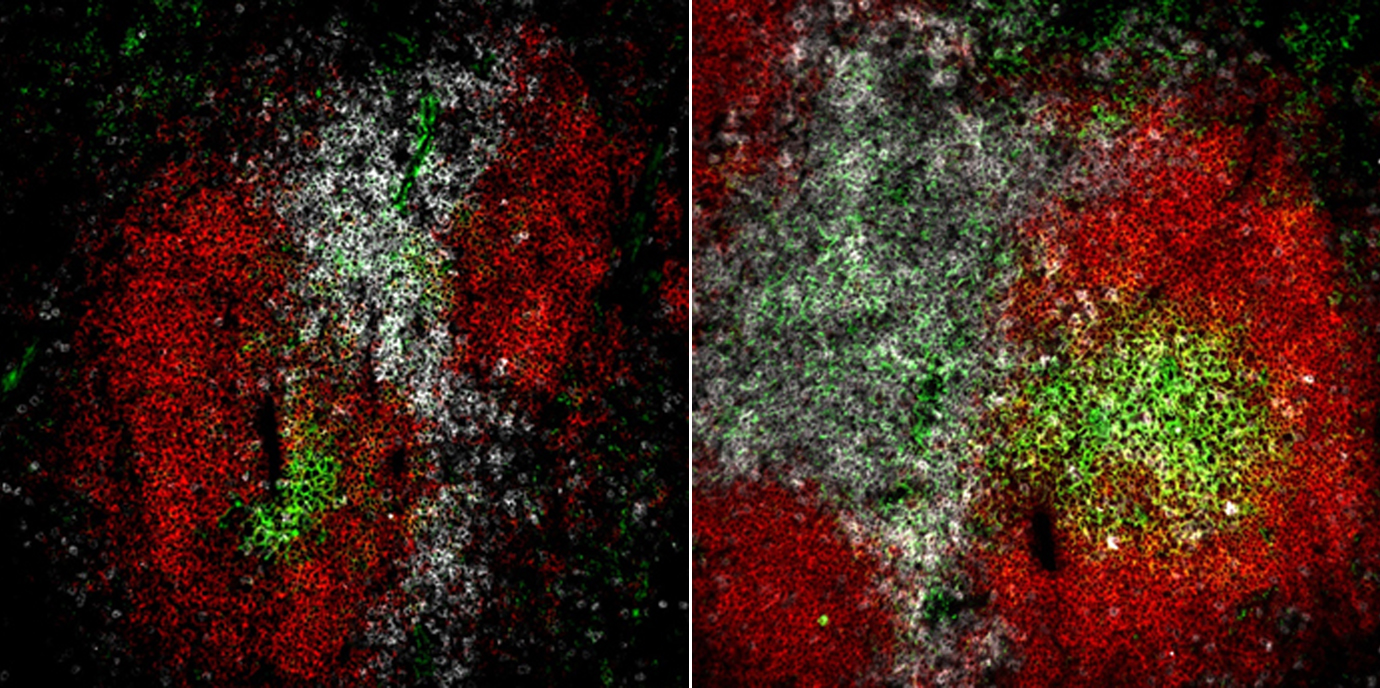

Autoimmunerkrankungen wie der Systemische Lupus erythematodes (SLE) werden durch eine gestörte Immunregulation verursacht. Das Team um Natascha Kleiter vom Institut für Zellgenetik konnte nun einen neuen molekularen Mechanismus des nukleären Kernrezeptors NR2F6 in Immunzellen identifizieren, mit dem sich neue Wege zur gezielteren Immunsuppression erschließen könnten.(Bild: Kleiter/Cell Reports)

Ziel dieser Arbeit war es nun, den funktionellen und den molekulare Mechanismus von NR2F6 in follikulären CD4 Helfer und Keimzentrums B Zellen im Mausmodell aufzuklären. „Mäuse, denen der Kernrezeptor NR2F6 fehlt, bilden nach Immunisierung eine verstärkte Keimzentrumsreaktion mit erhöhter Zahl an follikulären CD4 Helfer Zellen, B Zellen und Plasma Zellen aus und entwickeln somit im Alter ein Krankheitsbild, das dem humanen SLE gleicht“, erklärt Erstautor und PhD-Student William Olson. In adaptiven Übertragungsexperimenten konnte das Team erstmals im Detail die Zell intrinsiche Rolle von NR2F6 in follikulären T Helfer Zellen untersuchen. Vor allem der pro-entzündliche Botenstoff Interleukin-21 verursacht die Überreaktion der T und B Zellen bei SLE. Nun konnten zum ersten Mal jene Bereiche identifiziert werden, an die NR2F6 in der Promoterregion des IL-21 Gens bindet. „Die Relevanz der erhöhten IL-21 Produktion konnten wir durch die spezifische Blockade des IL-21 Rezeptors in Mäusen ohne NR2F6 nachweisen, da dadurch die Akkumulatoin der T Helferzellen und damit die überschießende Immunreaktion eindrucksvoll verringert wurde“, ergänzt Olson.